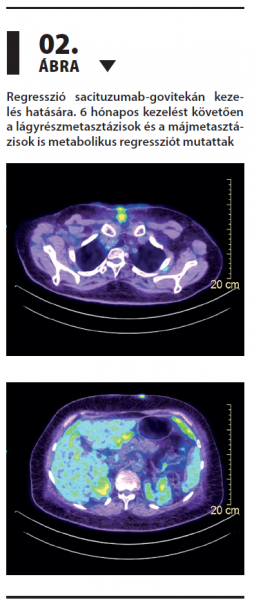

Antitest-gyógyszer konjugátum: sikeres terápia metasztatikus hormonreceptor-pozitív/HER2-negatív emlőtumoros beteg többedvonalas kezelése során